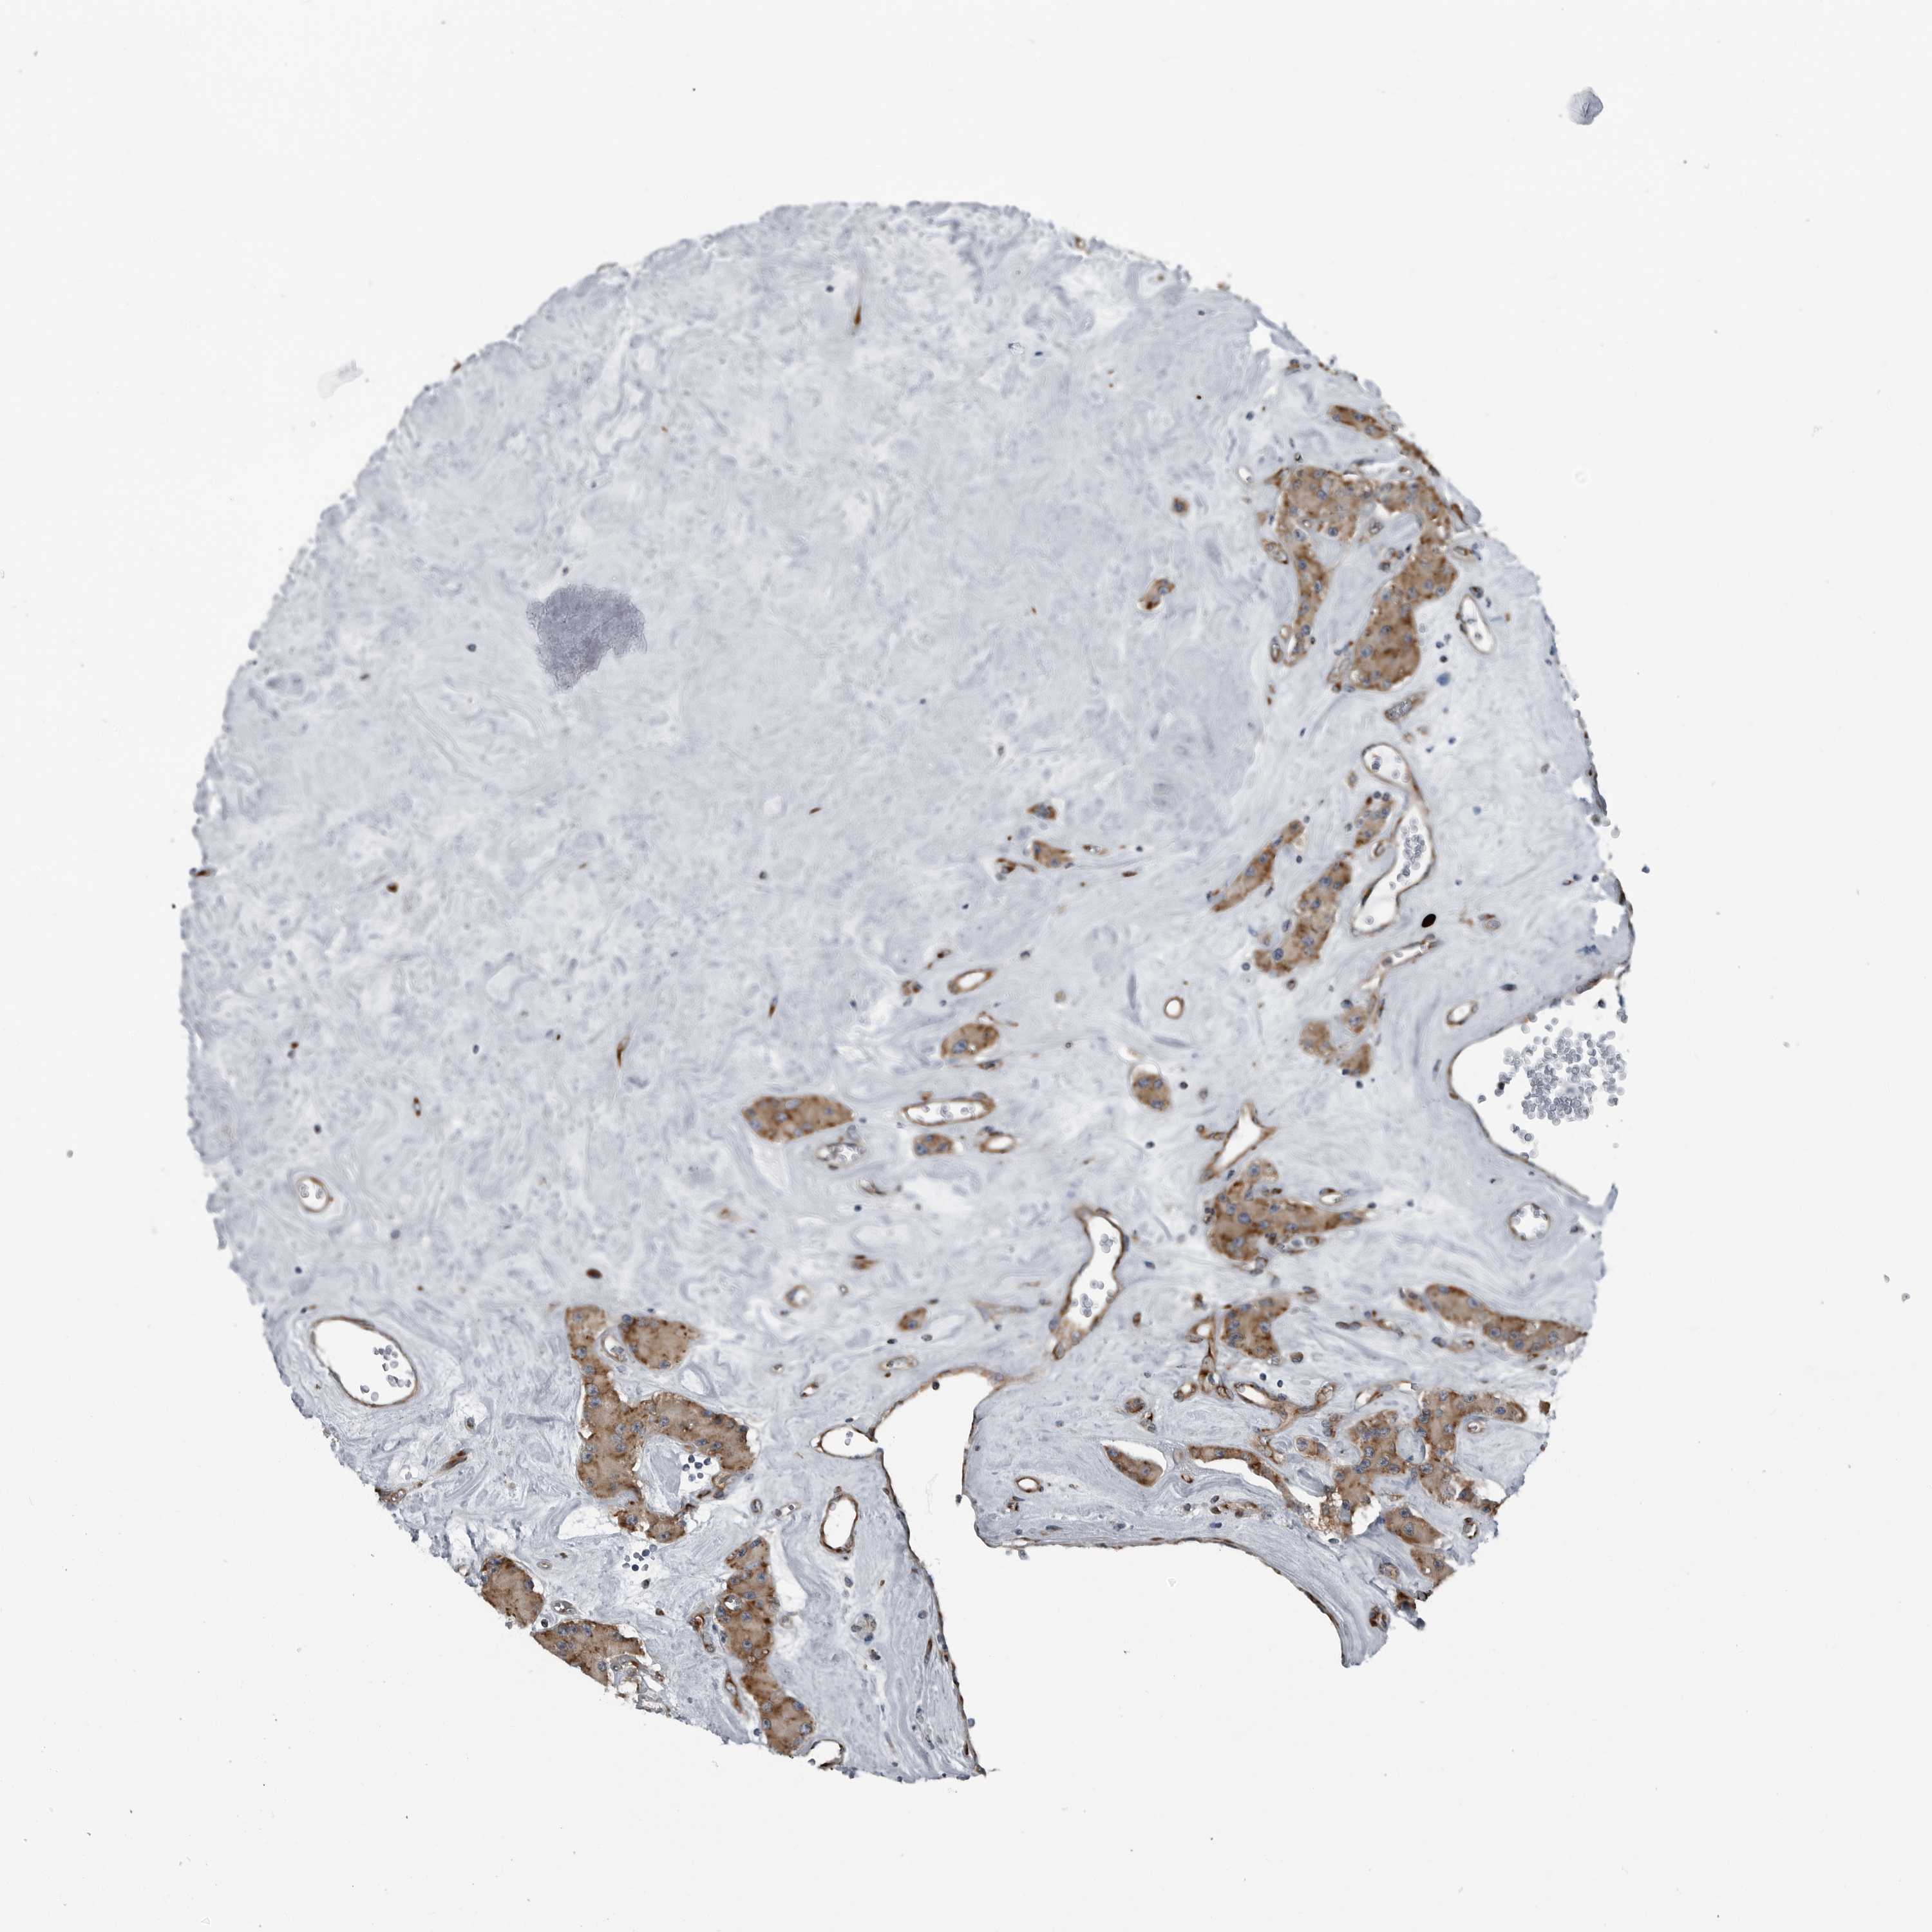

CEP85